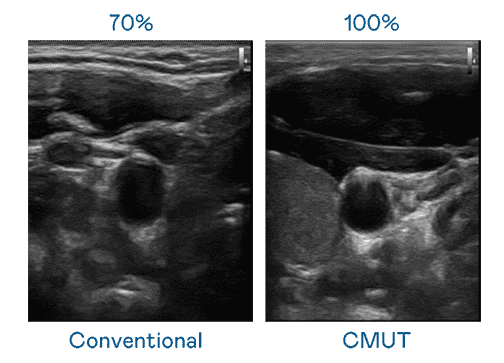

CMUT 技术是一种用电容式微机电元件来产生超音波讯号的技术。。。。与传统 PZT 压电式技术相比,,CMUT 频宽增加 30%,,,,更宽频的超音波讯号让影像解析度大幅提升,,是实现高影像品质医疗超音波扫描、、、、促进精准医疗发展的关键技术。。。。

大频宽带来超清晰影像

超音波影像的解析度高低,,,首先取决于探头能发出的讯号频宽。。森林舞会 CMUT 可提供高清晰的超音波讯号,,,,提供高频宽、、高灵敏度、、、、影像纹理细节更高的超音波影像,,,协助医护人员缩短影像判读时间及利用精准的医疗影像进行诊断。。。。